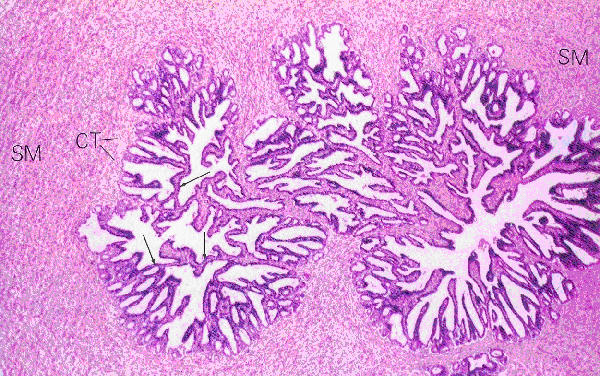

Vesicula seminalis

Seminal vesicle

SM: Smooth muscle

CT: Connective tissue

Source: Ross and Romrell plate 87 Figure 1 (p. 725)